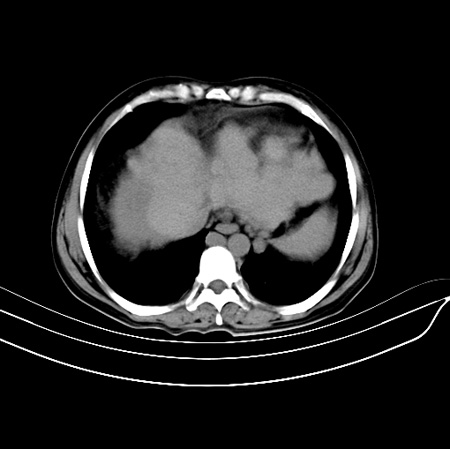

以下是引用江尾海头在2007-9-7 19:01:00的发言:[br]肝叶比例失调,肝边缘高低不平,尾状叶增大,肝裂增宽。肝右叶见较大密度减低影,边缘欠清。脾脏明显增大,胃底及奇静脉半奇静脉曲张。胆囊未见明显显示。 考虑:1、肝癌。2、肝硬化伴脾大静脉曲张。

以下是引用zhangxu5888在2007-9-7 22:31:00的发言:[br]1、肝硬化,食管 胃底及奇静脉半奇静脉曲张;2、脾脏肿大; 3、肝右叶的病灶呈锲性改变,内可见条片状钙化,边界清晰,密度明显低于周围正常肝组织,我觉得肝癌可能性不是很大, 同意楼上观点,有可能是栓塞,建议增强.